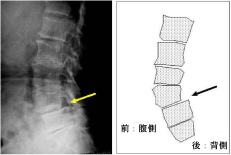

足のしびれ・痛み

腰髄

腰椎すべり症

頸椎椎間板ヘルニヤ